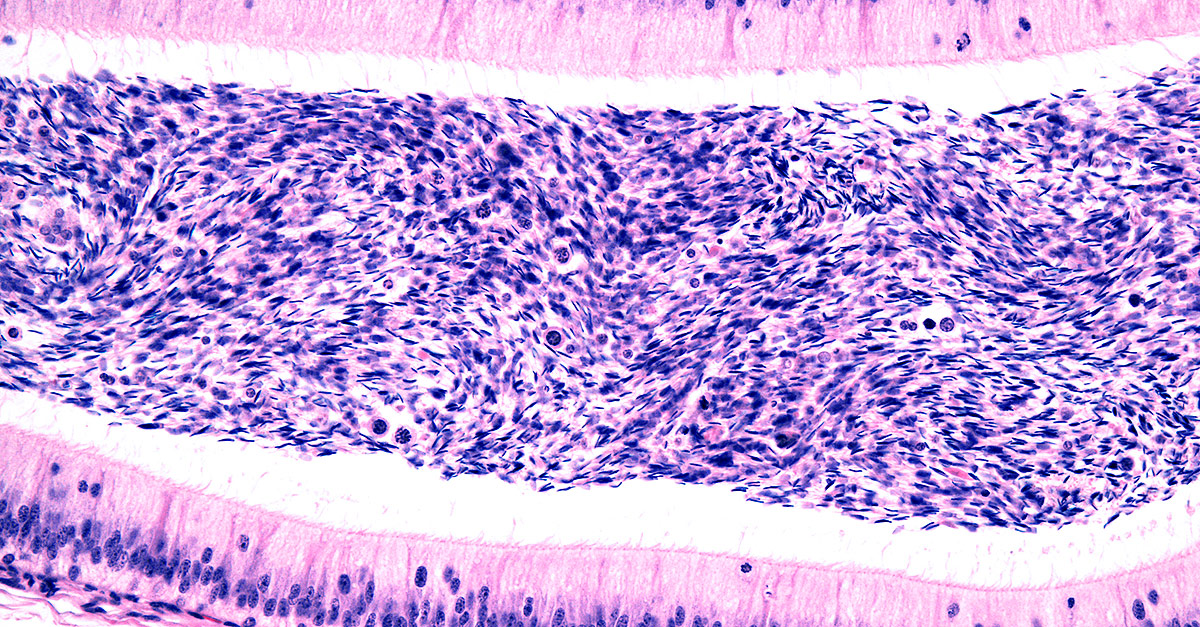

Inflammation of the epididymis can be painful and dangerous. Here’s what you need to know.